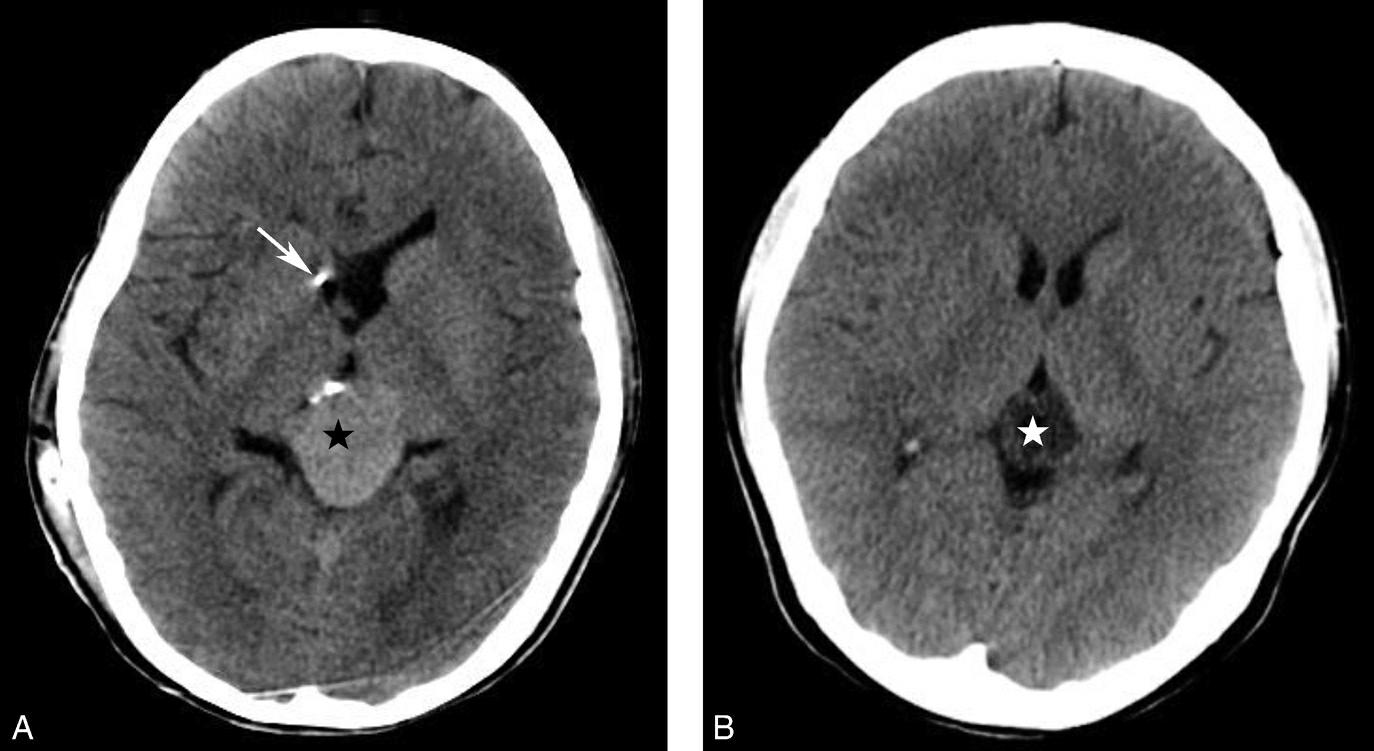

蝶鞍两侧为海绵窦,其内包含颈内动脉及第Ⅲ~Ⅵ对脑神经。海绵窦的密度升高或体积增大常提示病变存在。海绵窦外侧为颞叶,两者之间隔以海绵窦外侧壁。鞍背后方为桥前池及其后方的脑桥,桥前池内可见基底动脉断面,呈圆形稍高密度影。层面中部两侧为颞骨乳突部,其内气化的骨性腔隙为乳突气房。脑桥后方为第四脑室,呈半圆形或新月形,小脑半球的病变(如肿瘤、炎症、出血等)常压迫第四脑室,导致其变形甚至闭塞(图1-2-13)。两侧小脑半球间为小脑蚓部。小脑半球与颞骨乳突部间可见乙状窦。小脑蚓部后方为直窦与上矢状窦汇入窦汇处,窦汇两侧为横窦。静脉窦血栓时可见上述静脉窦增宽、密度明显升高(图1-2-14)。

图1-2-13 第四脑室变形(小脑转移瘤)

A.第四脑室受压变形右移(白箭),提示左侧小脑半球病变;B.左侧小脑半球环形强化结节(黑箭),为瘤体,其周围伴有低密度水肿区